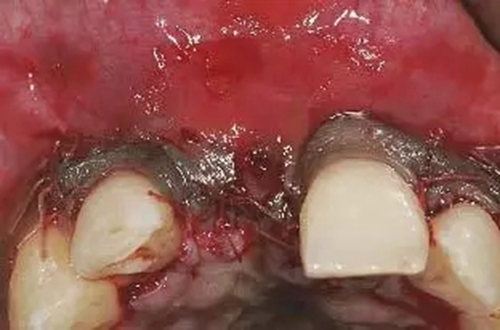

圖3、拔牙后看到更大范圍的骨缺損,并且缺損導(dǎo)致上頜側(cè)切牙根尖牙骨質(zhì)暴露,繼而存在術(shù)后由于軟硬組織退縮而帶來的美學(xué)風(fēng)險(xiǎn)。

圖7、去除了肉芽組織和根尖感染組織,仔細(xì)沖洗后,可見雙側(cè)拔牙窩唇側(cè)骨壁有大面積缺損。

圖8、植入2顆Camlog平行壁螺紋種植體,扭矩達(dá)35Ncm。安放兩個(gè)粗直徑的愈合帽,防止軟組織退縮和凹陷。